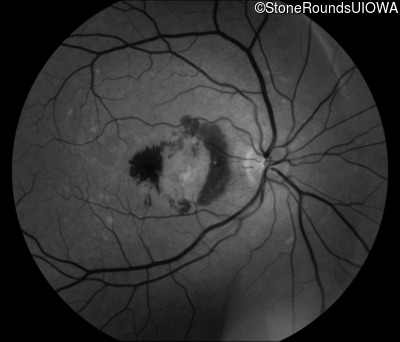

Fundus Photography - Right - 20/250